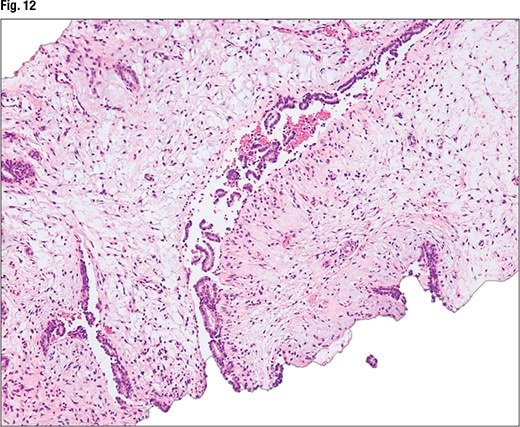

The third case Dr. Li presented is that of a 50-year-old female who presented with a 12-cm well-circumscribed breast mass. In the core biopsy, “we can see biphasic proliferation with epithelial proliferations and stromal proliferation. The biopsy is kind of fragmented,” and there’s some stromal heterogeneity in terms of the cellularity, with some areas showing more stromal cellularity and others less (Fig. 9). At higher power (Fig. 10), intratumoral heterogeneity can be seen. In Fig. 11, tissue fragmentation can be seen. Under higher magnification (Fig. 12), “there’s no severe cytologic atypia and virtually no mitosis in the stromal components.”